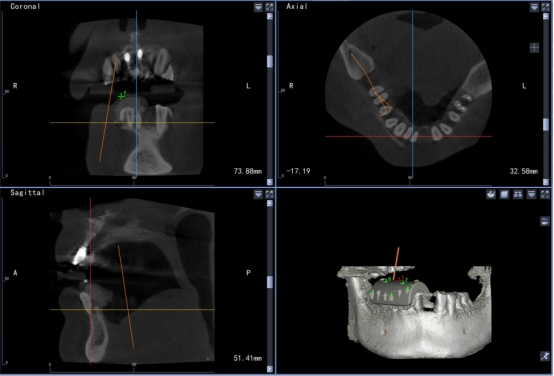

目前,小艾电竞 拥有全球领先的口腔种植动态导航系统,口腔修复种植科主任董强、副主任田艾带领下的医护团队,大量开展全数字化口腔种植修复治疗。通过使用口腔种植动态导航系统,使种植技术更加“精准、安全、微创、高效”。

高精准度:采用国际领先的红外光学定位技术,准确为医生指引方向,准度可达到0.3mm,种植体植入方向、位置、角度、深度一目了然,确保了种植手术的可预期性,显著提高种植精度。

成功率高:术前口内模拟种植,避开神经血管,设计种植方案,运用计算机三维重建与可视化技术,清晰展现患者口内结构,保证了复杂病例的成功率。

实时引导:全程监控手术工具与解剖结构的位置关系,轻松把控种植位点、角度和深度,实时引导术者按计划进行种植。

数字化动态导航系统犹如口腔中的GPS导航”,简单来说就是通过虚拟数字化软件设计,提前设计好修复体三维位置,结合精准的红外光学定位技术,在种植手术过程中,实现全程实时的导航。使使种植医生实时监控和调整手术的进程。